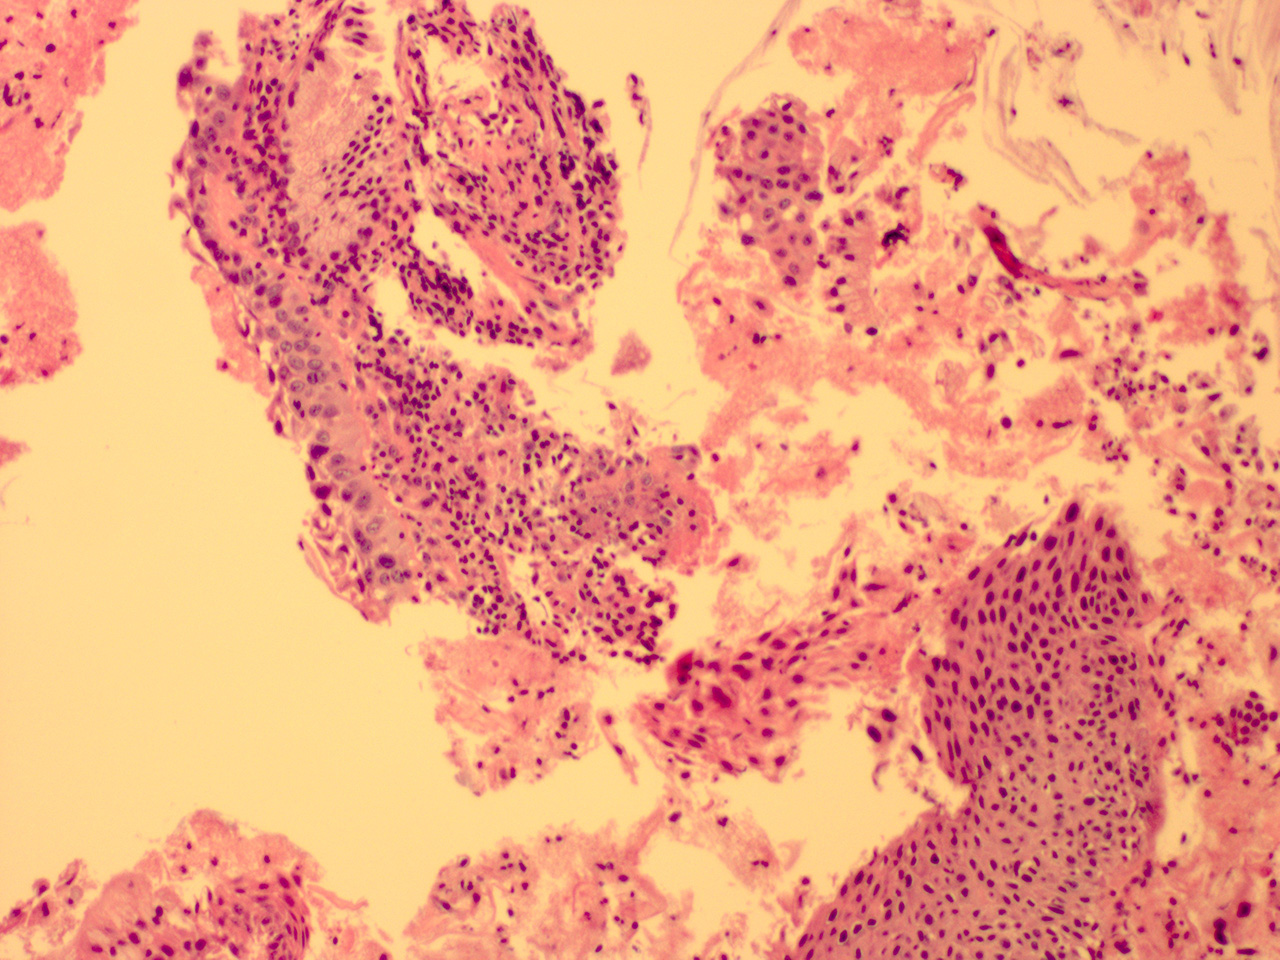

HGSIL Soft Bx

Low Power

HGSIL Soft ECC